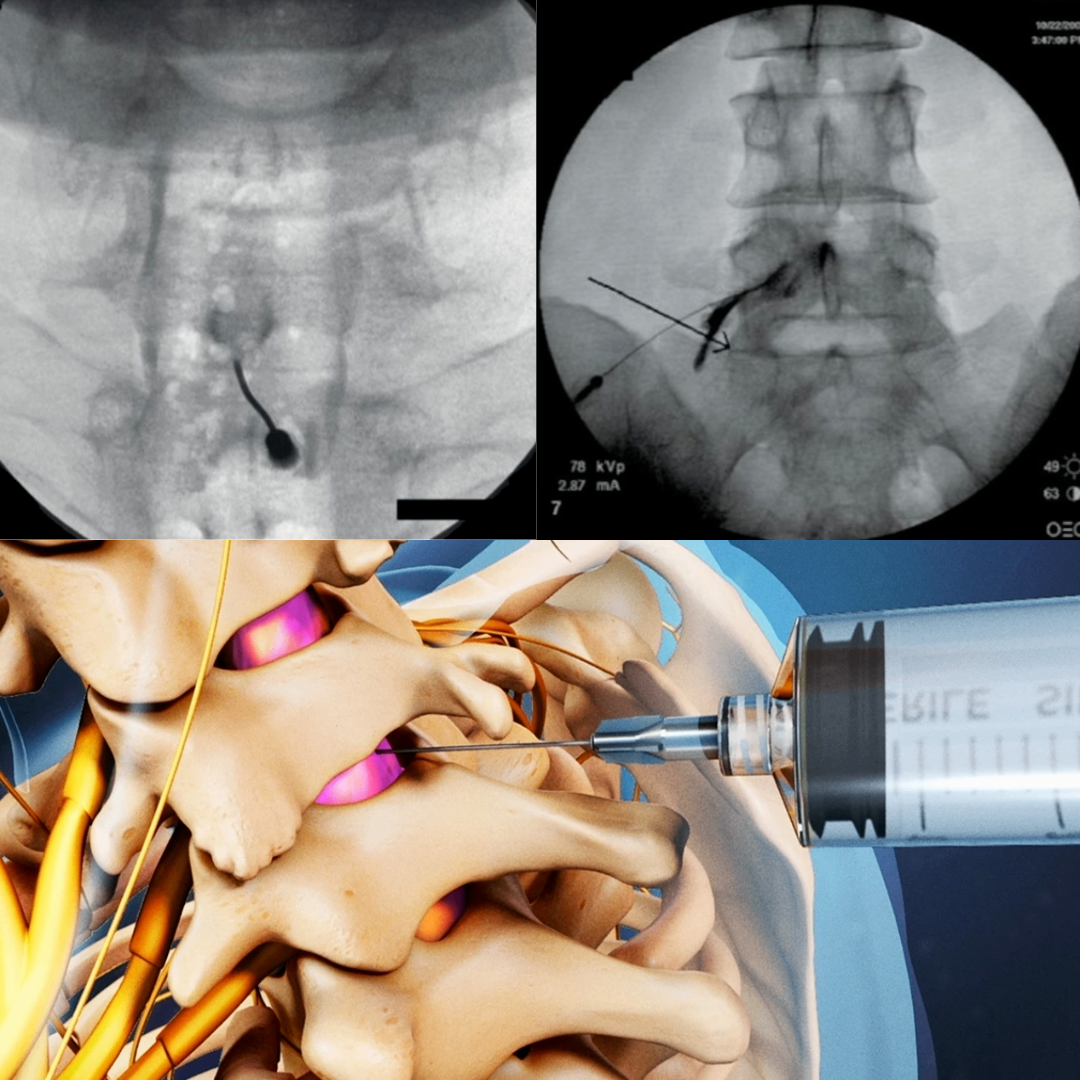

목/허리 디스크/협착증

목허리디스크 /협착증 환자는 씨암이라는 실시간 x-ray영상장치를 이용하여 치료합니다.

경추경막외 신경차단술,요추경막외 신경차단술,경추간공 신경차단술(영어를 번역하여 차단술입니다, 치료내용과 목적은  단순 차단술과 다릅니다)를 하여  디스크환자의 증상을 호전시킵니다.